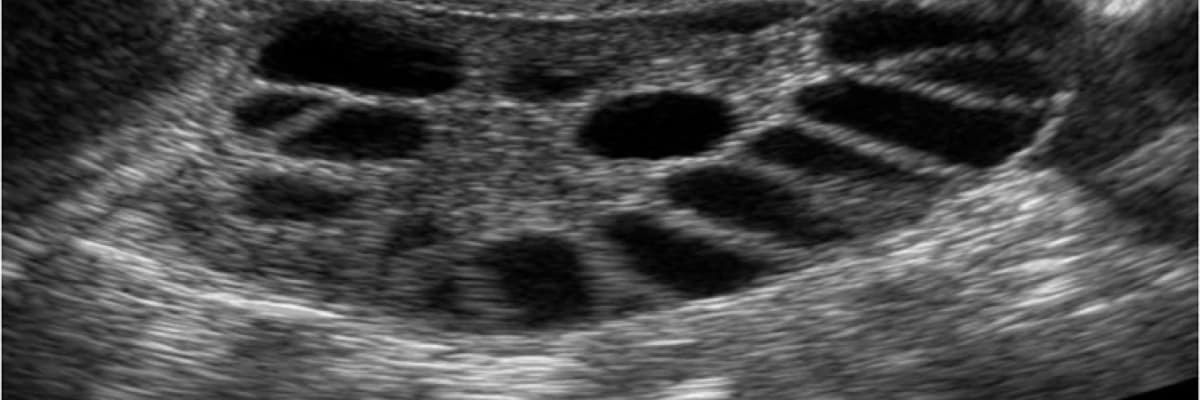

Polikistik over sendromu (PKOS) doğurganlık çağındaki kadınlarda sık görülen hormonal bir bozukluktur. PKOS olan kadınlarda genelde adet düzensizliği, adet görememe, aşırı tüylenme, sivilcelenme, aşırı kilo alımı ve evlilerde çocuk sahibi olamama gibi problemler görülür. PKOS genelde ergenliğe girmeyle başlayan bulgular verir. Ancak erken ergenlik döneminde yani ilk birkaç yıl bu bulgular normal genç kızlarda da görülebileceğinden ayırt edilmesi zordur. Bu nedenle tanı konması gecikebilir. Ergenlik dönemine benzer şikayetleri olan genç kızların PKOS gelişimi açısından daha dikkatli takip edilmesi gerekir. Bazı hastalarda daha geç yaşlarda kilo alımı, stres ve kötü beslenmeye bağlı PKOS bulguları ortaya çıkabilir. Bazen tanı koymak için bazı testler yapmak ve ultrasonla değerlendirmek gerekebilir. Ultrasonda yumurtalıklar normalden büyük görünür. İçlerinde minik-mercimek büyüklüğünde kistcikler görülür. Bunlar erken gelişme aşamasındaki yumurtalardır. Normal yumurtalıklarda da bunlarda 5-8 adet görülür. Ancak PCOS olan hastalarda yumurta gelişmesinin duraklamasına bağlı bu kistciklerden fazla miktarda (10-12’den fazla) görülür. PKOS’un tam olarak nedeni belli değildir. Ancak genelde ailesel yatkınlık vardır. Yani ailede kızlarda benzer bulguları olanlar vardır. Farklı bireylerde farklı bulgular görülebilir. Ama ana neden benzer hormonal bozukluklardır. Bu sorunlar kilo alımıyla daha da şiddetlenebilir.

• Ultrason bulguları: Ultrasonda polikistik overler mevcuttur. Yumurtalıklar normalden büyük ve içlerinde pek çok minik kistcikler görülür.

• Ultrason yapılarak özellikle rahim duvar kalınlığı ve yumurtalıkların büyüklüğü ve yapıları değerlendirilir.